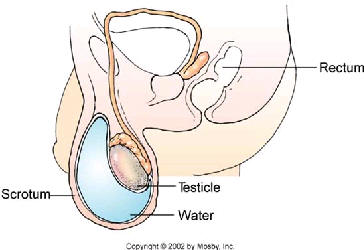

ففي التورم المائي في الصفن (القيلة) Hydrocele، يكون التورم نتيجة لتراكم سائل مائي فيما بين الاغشية التي تحيط بالخصيتين.

في كل تلك الحالات الثلاث يحدث تورم غير مؤلم في الصفن.

لا شيء من هذه الحالات الثلاث يسبب تلفآ مستديمآ للخصيتين. ومع ذلك فيجب عليك أن تذهب الى الطبيب إذا كان لديك أي تورم في الصفن حتى يمكنه أن يستبعد الاسباب الاخرى.

ويمكن عن طريق الفحص بالموجات فوق الصوتية مساعدة الطبيب على تحديد التشخيص.

وتكون ثمة حاجة لعلاج هذه الحالات الثلاث فقط إذا كان التورم مسببآ لعدم الارتياح أو إذا زاد حجمها. فبعد أن يقوم الطبيب بتخدير المنطقة موضعيآ قد يعمب على بزل (شفط أو سحب) السائل المتراكم باستخدام ابرة ومحقن، ثم يحقن مادة لمنع السائل المتراكم كبيرة ججدآ، فغالبآ ما تكون هناك حاجة للتخلص من السائل ولمنع تراكمه في المستقبل.